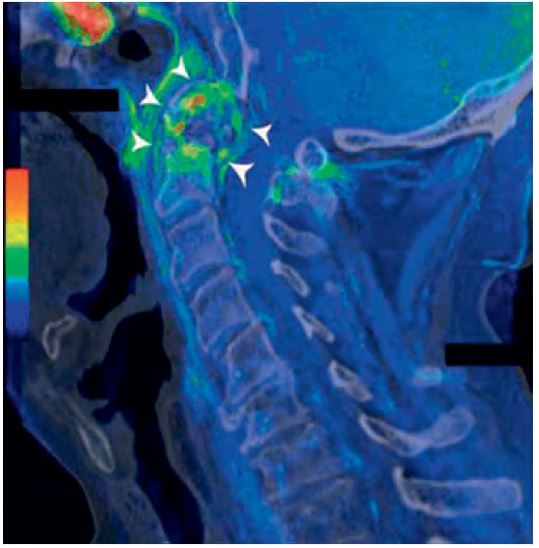

La columna cervical posee una estructura única que le confiere un amplio rango de movimiento, especialmente en sus tres segmentos superiores: las articulaciones atlantooccipitales y atlantoaxiales. En condiciones normales, la movilidad cervical requiere una sincronización precisa entre todos los elementos vertebrales. Sin embargo, en presencia de enfermedad, una alteración en un solo nivel puede generar disfunción en otros segmentos.

Para los anestesiólogos, comprender esta dinámica es crucial al evaluar pacientes con dolor cervical, ya que permite identificar limitaciones funcionales que podrían estar relacionadas con patologías subyacentes como radiculopatías, mielopatías o incluso insuficiencia vertebrobasilar.

Estas maniobras deben realizarse con precaución en pacientes con síntomas de mielopatía, radiculopatía o insuficiencia arterial, ya que podrían precipitar eventos neurológicos agudos. También se recomienda especial cuidado en pacientes con artritis reumatoide, debido al riesgo de inestabilidad cervical por erosión de la apófisis odontoides.